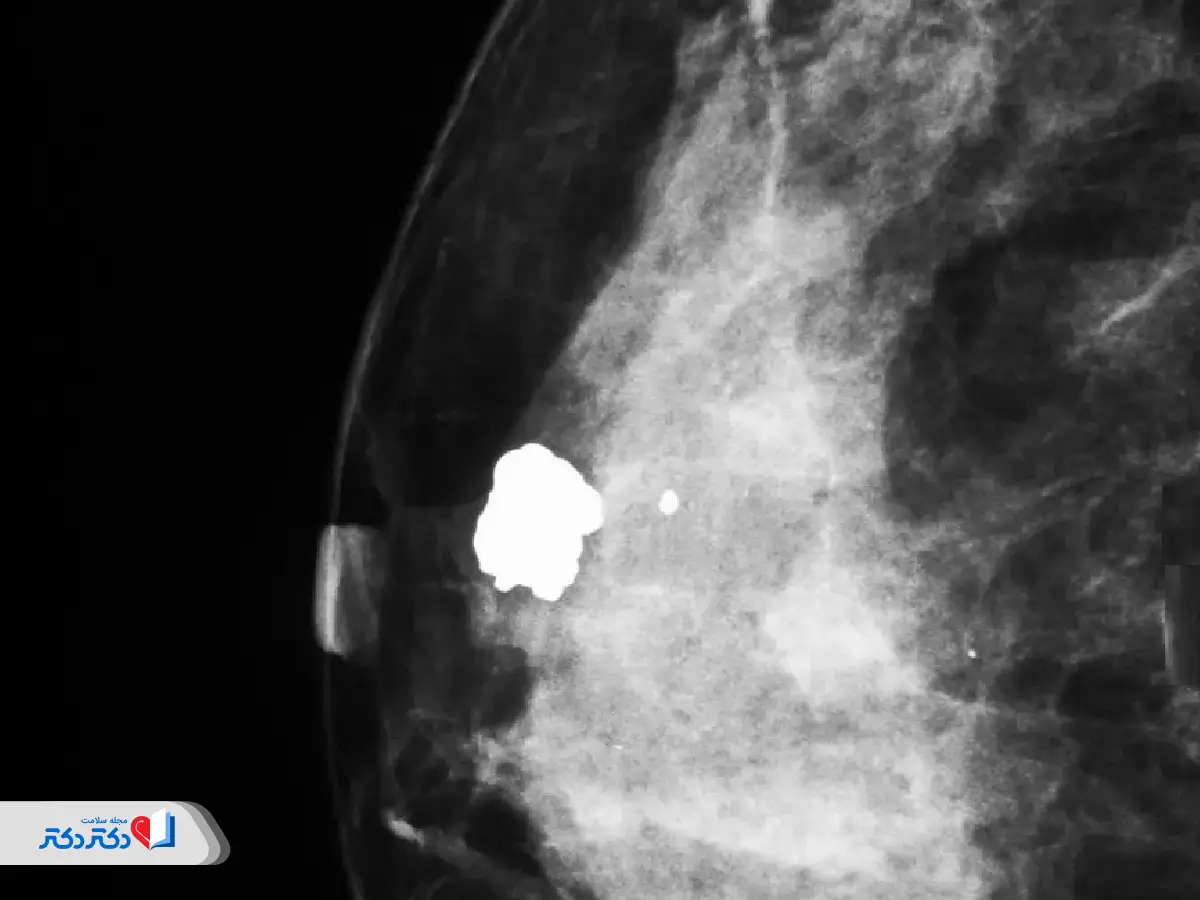

عکس ماموگرافی نرمال و مشکوک

باید بدانید که تفسیر عکس ماموگرافی و نوع عارضه احتمالی وظیفه متخصص رادیولوژی و پزشک است. به علاوه گاهی ماموگرافی بهتنهایی برای تشخیص نهایی کافی نیست؛ بهویژه در مورد خوشخیم یا بدخیم بودن توده. برای آشنایی بیشتر شما در زیر چند نمونه عکس ماموگرافی مشاهده میکنید. ولی فراموش نکنید که بسته به نوع عارضه، تراکم بافت پستان و دقت تصاویر ممکن است عکس ماموگرافی شما متفاوت از عکسهای زیر باشد.